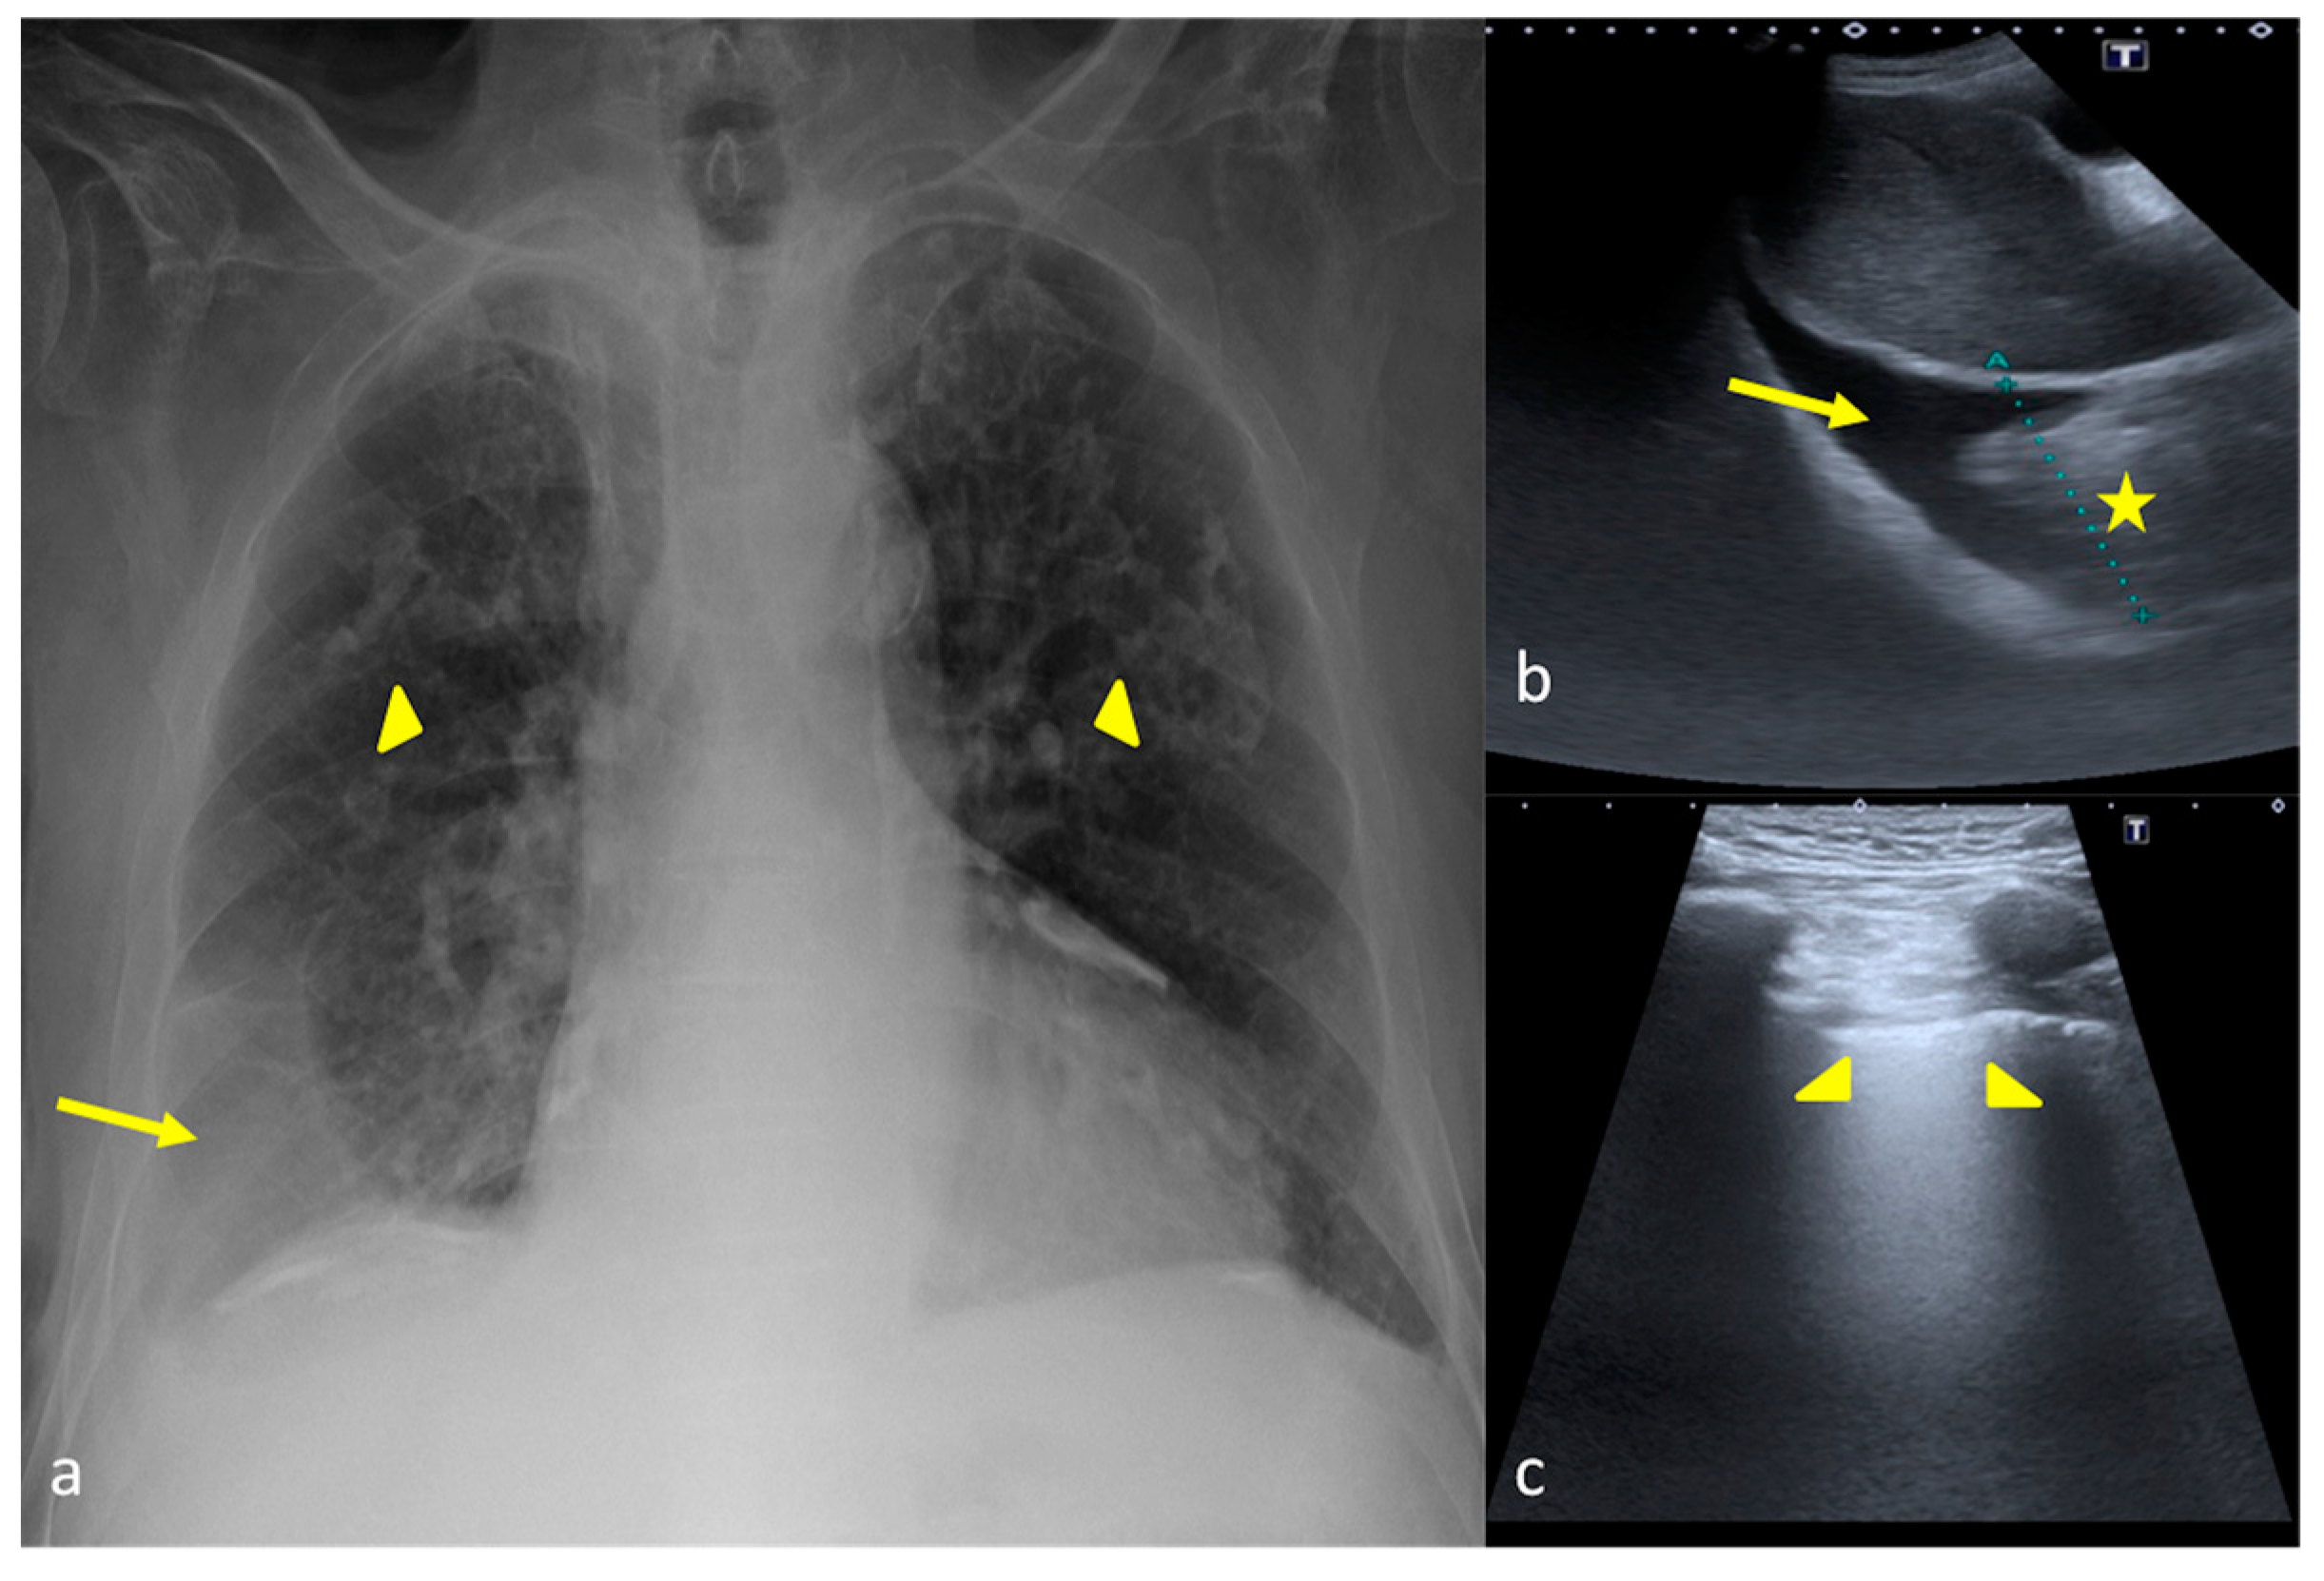

Figure 11.

A 79-year-old male patient suspected of having pulmonary edema. CXR (a) and LUS (b,c). (a) On the CXR opacity of the middle and inferior field was detected bilaterally (a, arrowheads) with right lung basis consolidation (a, arrow). (b,c) LUS integration showed on the right lung basis (b) a pleural anechoic effusion (b, arrow) associated with a consolidative area (b, star); the evaluation of the right and left lungs (c) showed a compact appearance of the B-lines on the explorable lung areas in the intercostal space (c, arrowheads). In this case LUS allowed us to better clarify the nature of the CXR lung opacities.